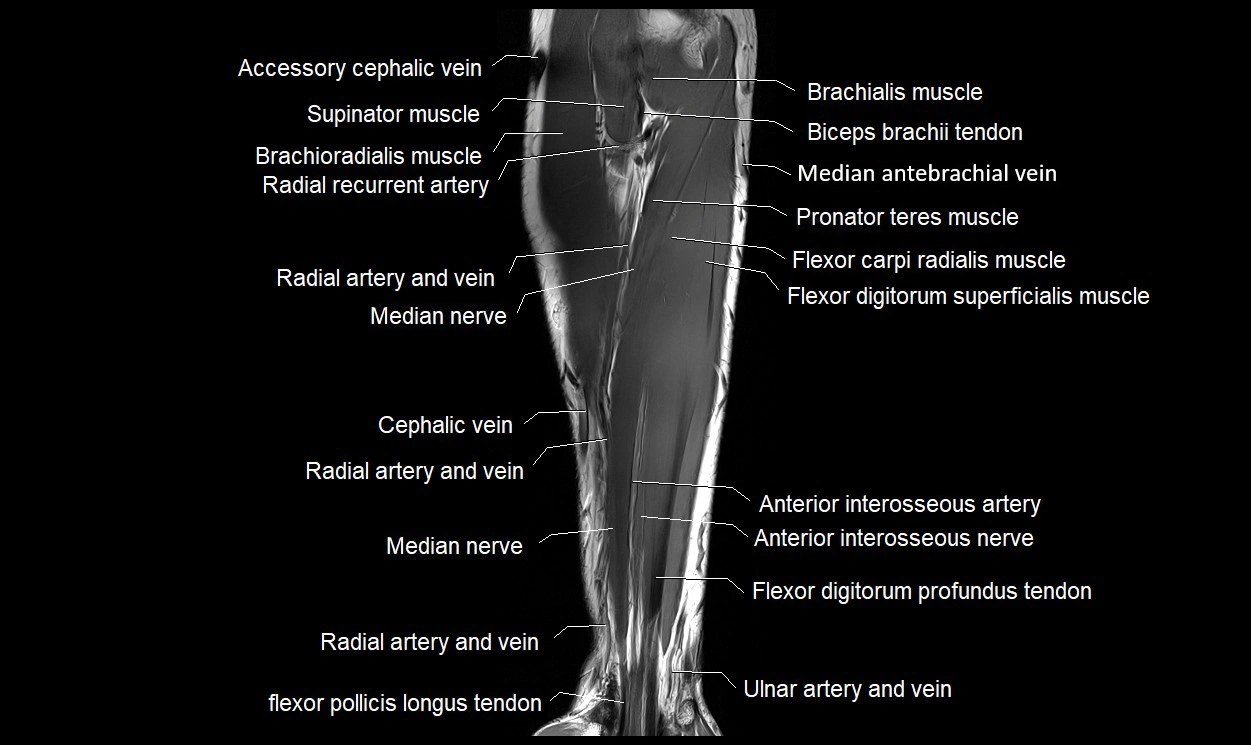

MRI images

image